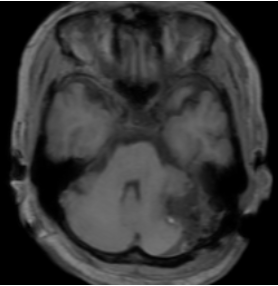

症例④:動脈瘤クリッピング

| 治療内容 | 左内頸動脈に7mmの動脈瘤があり、視神経を圧迫していました。脳、血管、神経を保護しながら4本のクリップをかけました。 |